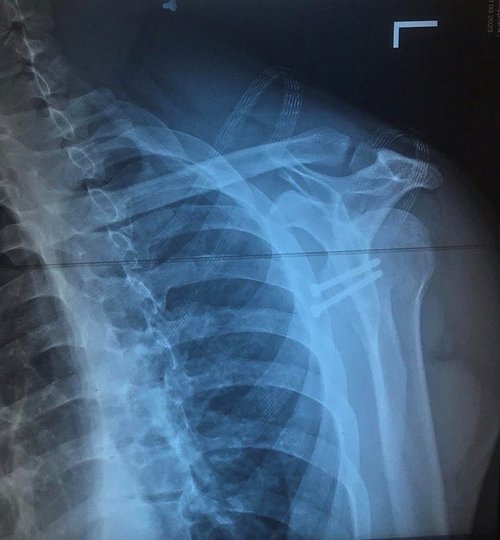

Хірурги Волинської обласної лікарні провели складну операцію військовому, в якого були численні вивихи плеча. Перший вивих йому вправили товариші по службі, але після цього вивихи ставались все частіше і частіше. Коли чоловік вже не міг нормально рухати рукою, він звернувся за допомогою. Спершу чоловіка направили у Дніпро, а тоді у Луцьк, де хірурги Волинської обласної лікарні стабілізували плечовий суглоб.

Про успішно виконану операцію прес-служба Волинської обласної клінічної лікарні повідомила у середу, 29 березня. Як розповів сам військовий, перший вивих плечової кістки він отримав під час бойових дій ще десять місяців тому. Вивих вправили товариші по службі. Був великий крововилив в суглоб і навколо суглоба, але за медичною допомогою чоловік не звертався.

Орієнтовно через місяць стався повторний вивих плеча. В подальшому вивихи повторювалися все частіше і частіше, навіть за найменших рухів. Чоловік пройшов МРТ, під час якого виявили травматичне пошкодження лівої лопатки. Пораду про необхідність операції військовий проігнорував.